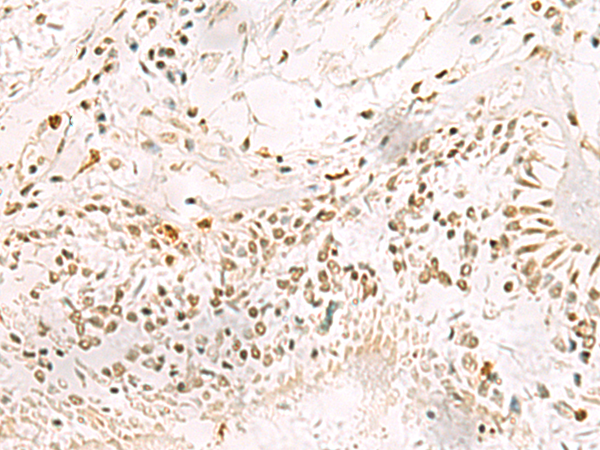

IHC positive control: |

Human gastric cancer and Human lung cancer |

IHC Recommend dilution: |

50-200 |